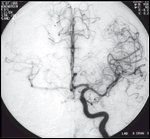

FIGURE 5

Contralateral Cerebral Blood Vessels

Our method of internal carotid balloon occlusion performed under local anesthesia with monitoring of mental functions for 20 minutes seems to be reliable in predicting a patient's tolerance to the interruption of carotid blood flow. More recently, we have relied on angiographic evidence of adequate contralateral cerebral blood without performing elective internal carotid balloon occlusion (Figure 5).

In our study of 28 patients undergoing cerebral angiography, 26 (93%) demonstrated angiographic or balloon occlusion testing evidence of tolerance to possible carotid sacrifice.[ 28] With this preoperative information, surgical decisions about carotid bypass options can be made. Even with preparation for internal carotid artery grafting, a review of multiple series reports a 9.7% rate of strokes and a 2.4% incidence of mortality.[50]